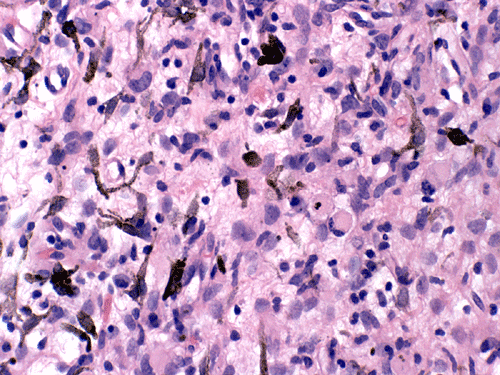

At low magnification, the lesion appears as a spindly, desmoplastic neoplasm with storiform arrangement that could be seen in some mesenchymal tumors (Panel A). On higher magnification, the overall pleomorphism is relatively mild. Mitotic figures are not readily seen. There are some round to triangular cells that are surrounded by a rim of retraction artifactual space from the surrounding desmoplastic component  (Ţ in Panel B). These cells seem like a drop of oil floating on water. The morphologic features of these cells are suggestive of ganglionic cells and/or gemistocytic astrocytes. In other areas, tumor cells containing melanin pigment (Panel C) are present. Deposition of reticulin material can be seen essentially around every single cells (Panel D). Scattered within the tumors are large ganglionic that can be well demonstrated by immunohistochemistry for synaptophysin (Panel E). Tumor cells with mature neuronal phenotype is also immunoreactive for NeuN (Panel F). Immunohistochemistry should that the amount of astrocytic cells far out numbered ganglionic cells (Panel G). Cells that express melanin are also strongly positive for HMB45 on immunohistochemistry.

Microscopically, the desmoplastic activity is so widespread that it would suggest sarcomas to the novices. Recognition of this potential pitfall is of importance during intraoperative consultations. DIA and DIG have known tendency to extend into the Vichow-Robin space. However, there is a typical, marked demarcation between the desmoplastic tumor and the cortex. Spindle cells arranged in fascicles, storiform, or wholed pattern intermixed with collagenous component are common findings and is particularly associated in areas with leptomeningeal involvement. On detailed examination, neoplastic  neuroepithelial cells with features of astrocytes, gemistocytic astrocytes, and neurons (ganglion cells) are common. It is very common that the gemistocytic astrocytes and ganglionic cells have a retraction, artifactual space at their cytoplasmic border. These large cells appear like drops of oil in water (i.e., the desmoplastic component). The collagenous component will stain blue and the neuroepithelial component will stain pink or red on Masson’s trichrome. A reticulin stain will show deposition of reticulin material around individual tumor cells. Significant nuclear pleomorphism is not a usual feature of these tumors. Mitosis is quite uncommon and the Ki-67 labeling index for cyclinc cells ranges from less than 0.5% to 5% 2. Necrosis and endothelial proliferation should not be seen. The glial component can be well demonstrated by immunohistochemistry for GFAP. The ganglionic component can be well demonstrated by immunohistochemistry for synaptophysin, neurofilament proteins, synaptophysin, NeuN, class III beta-tubulin and MAP2.

Although melanotic differentiation is one way to explain the presence of melanocytic cells in the tumor under discussion, the melanocytic cells may also represent colonization by melanocytes that are recruited from the leptomeninges. Embryologically, the neurocrest cells are the origin of the telencephalic leptomeninges and also melanocytes that populate the skin and other tissues including the leptomeninges. An increased density of melanocytes in the leptomeninges is commonly found in people with dark skin and the patient under discussion is an African American. In fact, melanocytic colonization has been described in a meningioma that is taken from a 70 year-old African American patient 14. Similar melanocytic colonization has been described in non-melanocytic tumors arising in skin and breast where recruitment of melanocytes seems to be possible 15, 16.

On one hand, melanotic differentiation is not uncommon in neuroepithelial tumors with glial and/or neuronal component. The melanotic cells in the tumor under discussion may well represent melanotic differentiation of the neuroepithelial component.  From the morphological point of view, however, the melanotic cells under discussion appear small, elongated and somewhat similar to melanocytes that could be seen in leptomeninges. When these features are interpreted in conjunction with tumor involvement of the leptomeninges in a dark skinned person (African American) as in the current case, the possibility of melanocytic colonization by non-neoplastic leptomeningeal melanocytes seems equally possible.